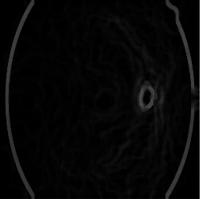

Fig - 1:Bloodvesselsandopticnerveinafundusimageof retinalimage.